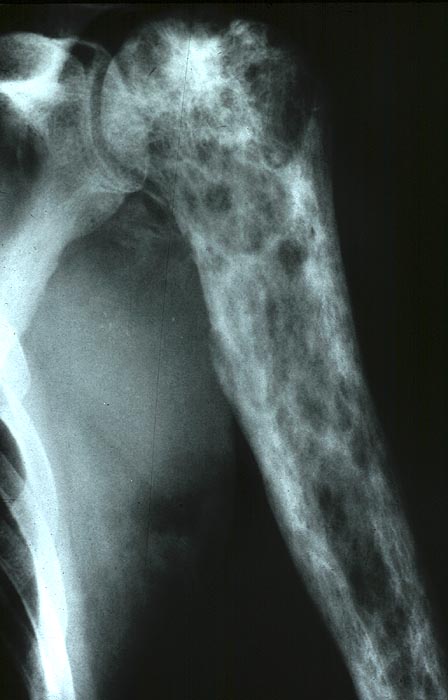

PathoPic ID 5039 - Chondrosarkom

Chondrosarkom

maligner Tumor

Knochen, Humerus

Knochen, Knorpel, Gelenke

Neben lytischen Veränderungen Ablagerung von fleckförmig verkalkter Knorpelmatrix.

Radiologie

50